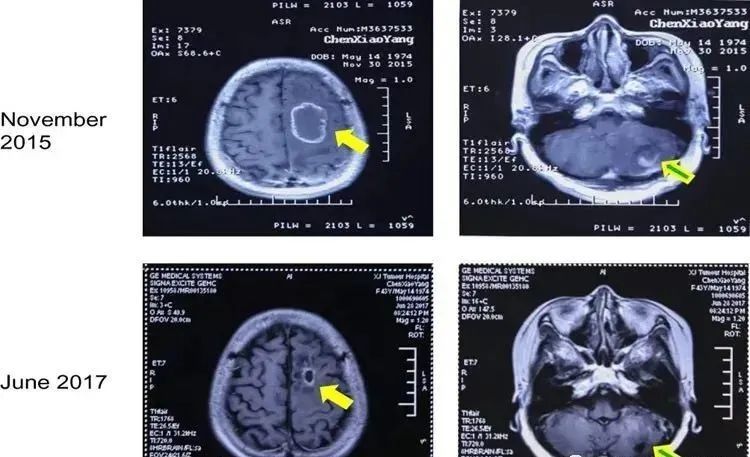

氢医学 吸氢气丨用吸氢机吸氢后 肺癌脑转移完全消失了 附案例 腾讯新闻